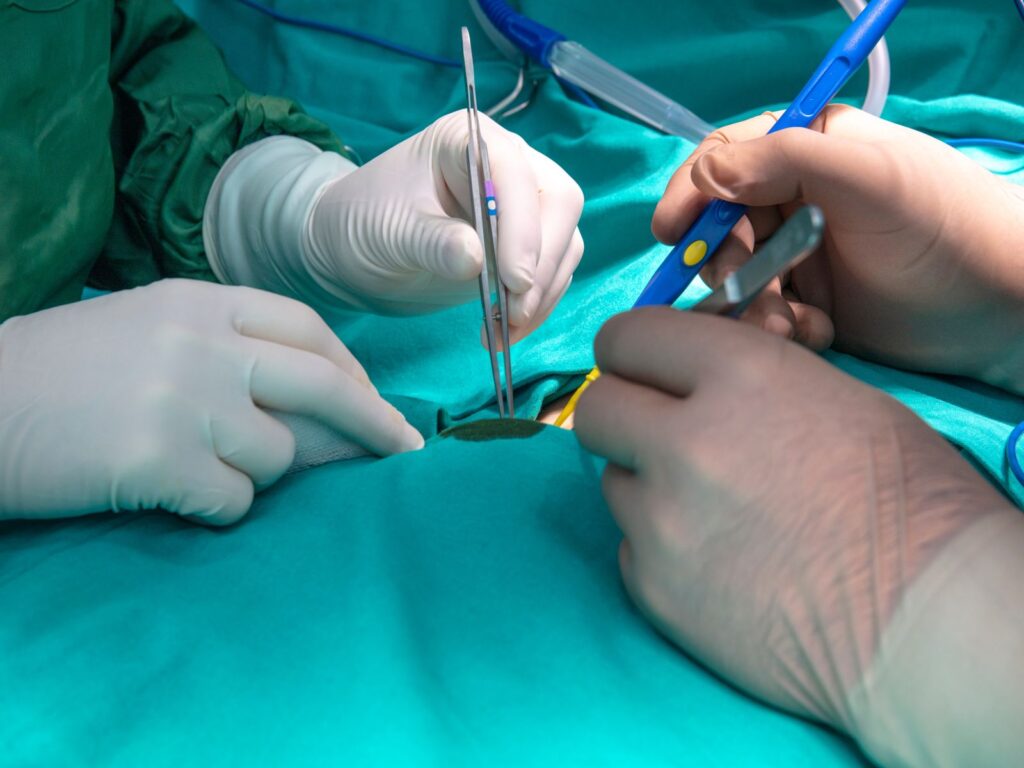

CHIRURGIE ORTHODONTIQUE

Les traitements chirurgicaux en orthodontie sont parfois nécessaires pour corriger des problèmes dentaires et maxillaires complexes qui ne peuvent être résolus par l’orthodontie seule. Dans notre cabinet, nous sommes dédiés à fournir des informations claires et rassurantes sur ces interventions, afin que vous et votre famille puissiez prendre des décisions éclairées et confiantes concernant votre traitement orthodontique.

Quand la chirurgie orthodontique est-elle nécessaire ?

La chirurgie orthodontique, aussi appelée chirurgie orthognathique, est envisagée lorsque des désalignements dentaires et maxillaires ne peuvent être corrigés uniquement avec des appareils orthodontiques. Ces interventions sont souvent recommandées pour améliorer la fonctionnalité, l’esthétique du visage, et la qualité de vie.

- Planification précise : Une évaluation détaillée et une planification minutieuse sont effectuées en collaboration avec des chirurgiens maxillo-faciaux.